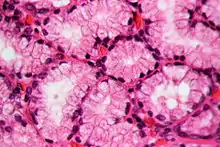

Histology

In staining during microscopic examination for diagnosis or research, acid dyes are used to color basic tissue proteins. In contrast, basic dyes are used to stain cell nuclei and some other acidic components of tissues.[8] Regarding cellular structures, acid dyes will stain acidophilic structures that have a net positive charge due to the fact that they have a negatively charged chromophore. Acidophilic structures include the cytoplasm, collagen and mitochondria. The two have an affinity for each other due to the conflicting charges.[9][10] Examples of acid dyes used in medicine include:[11]

- Lee's stain (stains reddish-pink).

- Phosphotungstic Acid Hematoxylin (PTAH) stain (stains blue).

- Eosin stain (stains pinkish-orange).